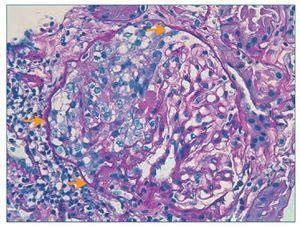

Figura 3. Histología renal caso 2 (tinción con ácido periódico de Schiff).

Semiluna celular (flechas) característica de las glomerulonefritis rápidamente progresivas en una fase activa y aguda.